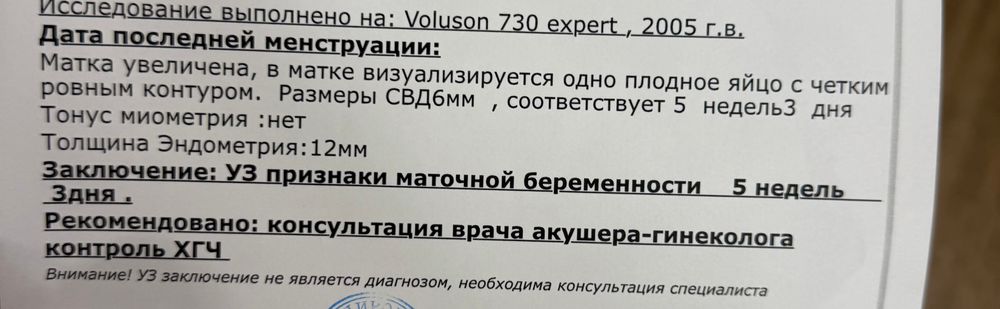

Девочки всем привет, сходила я на узи две недели назад, эмбрион двигался к нужному направлению, сказали вы рано пришли , сказали приходить через две недели, пришла сейчас через две недели сделать узи, сделали но сказали что срок должен быть уже 8 недель с последнего дня менструации и что размер не соответствует неделям, а соответствует 5 неделям +3

Размеры СВД 6мм, Эндометрия 12мм

отправили идти на хгч, боюсь плохих результатов , сталкивался ли кто с подобной ситуацией, когда отнимают две недели и не видно эмбриона на таком сроке.